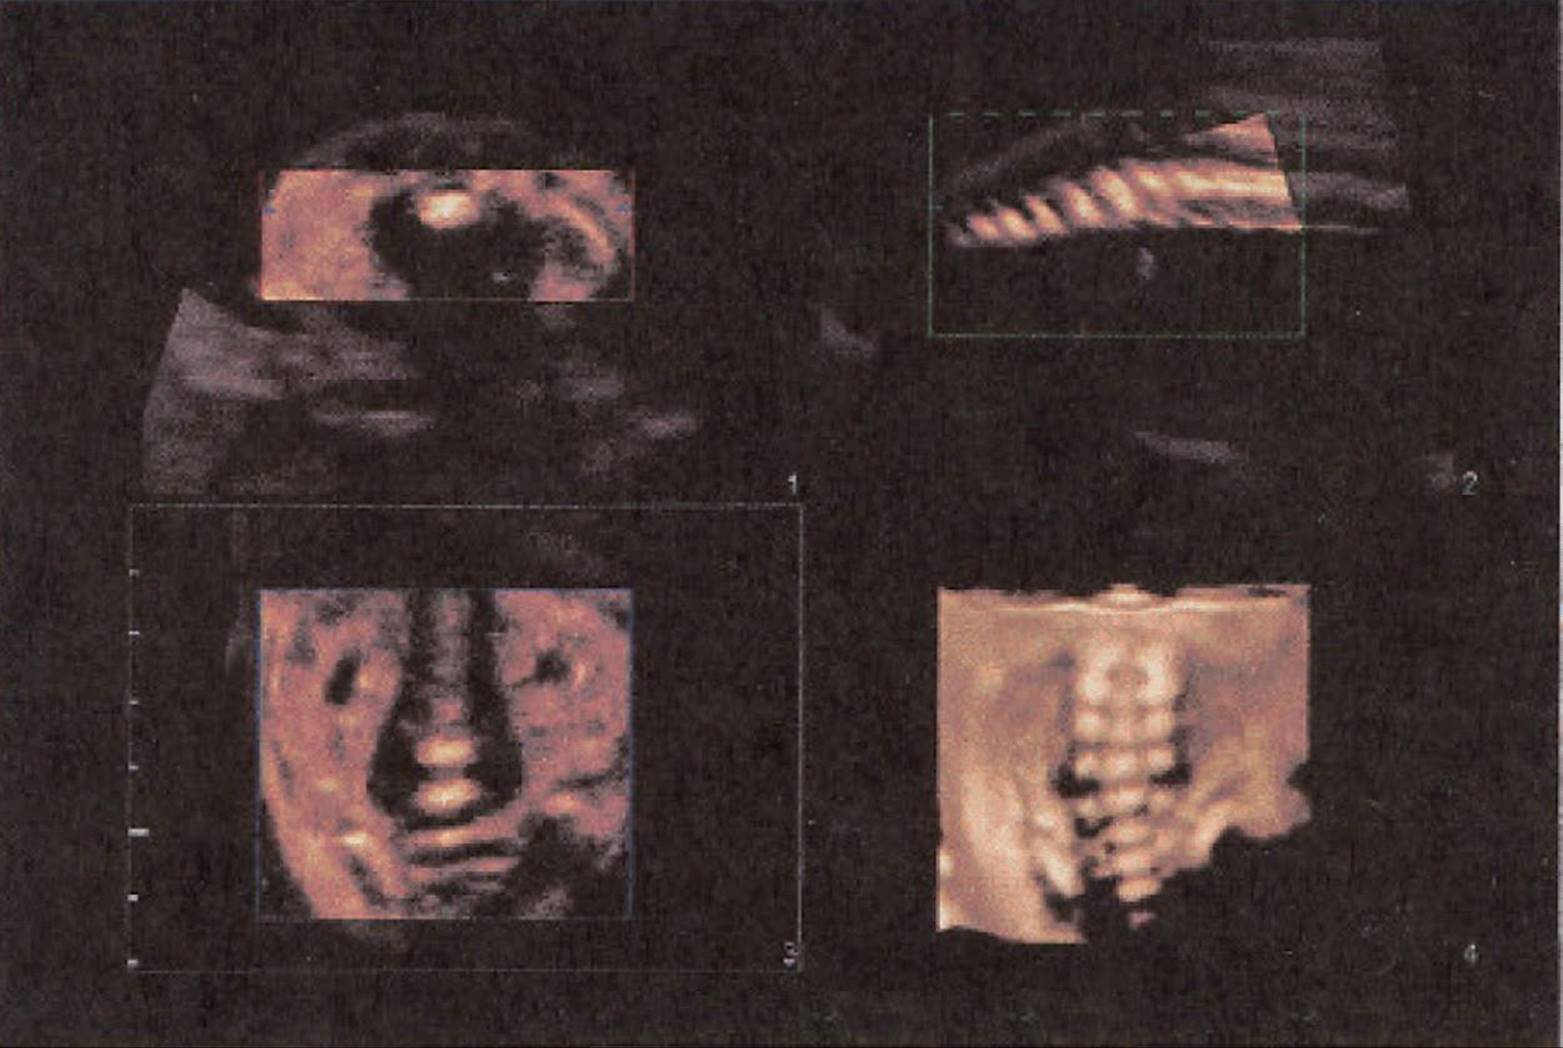

FIGURE 8–17. Multiplanar image of normal fetal spine. (Courtesy of Philips Healthcare.)

FIGURE 8–18. Multiplanar image of normal sacrum of a fetus at 26-weeks’ gestation. (Courtesy of Philips Healthcare.)